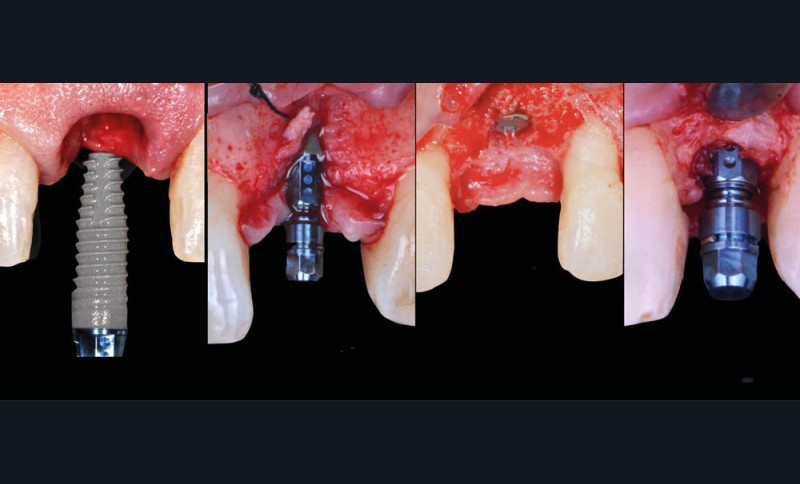

Lorsque le pronostic d’une dent en secteur esthétique est compromis, la solution implantaire est devenue fréquente. Le timing d’implantation [3] offre quatre options de traitement (fig. 1) en fonction de l’analyse clinique et radiographique préopératoire :

– Type 1 : la mise en place de l’implant se fait dans l’alvéole immédiatement après l’extraction et fait partie de la même procédure chirurgicale ;

– Type 2 : l’implantation précoce est réalisée 4 à 8 semaines après extraction. Le site présente une fermeture complète des tissus mous et une cicatrisation osseuse partielle ;

– Type 3 : l’implantation différée est réalisée 12 à 16 semaines après extraction. Le site présente une fermeture des tissus mous et une cicatrisation osseuse…